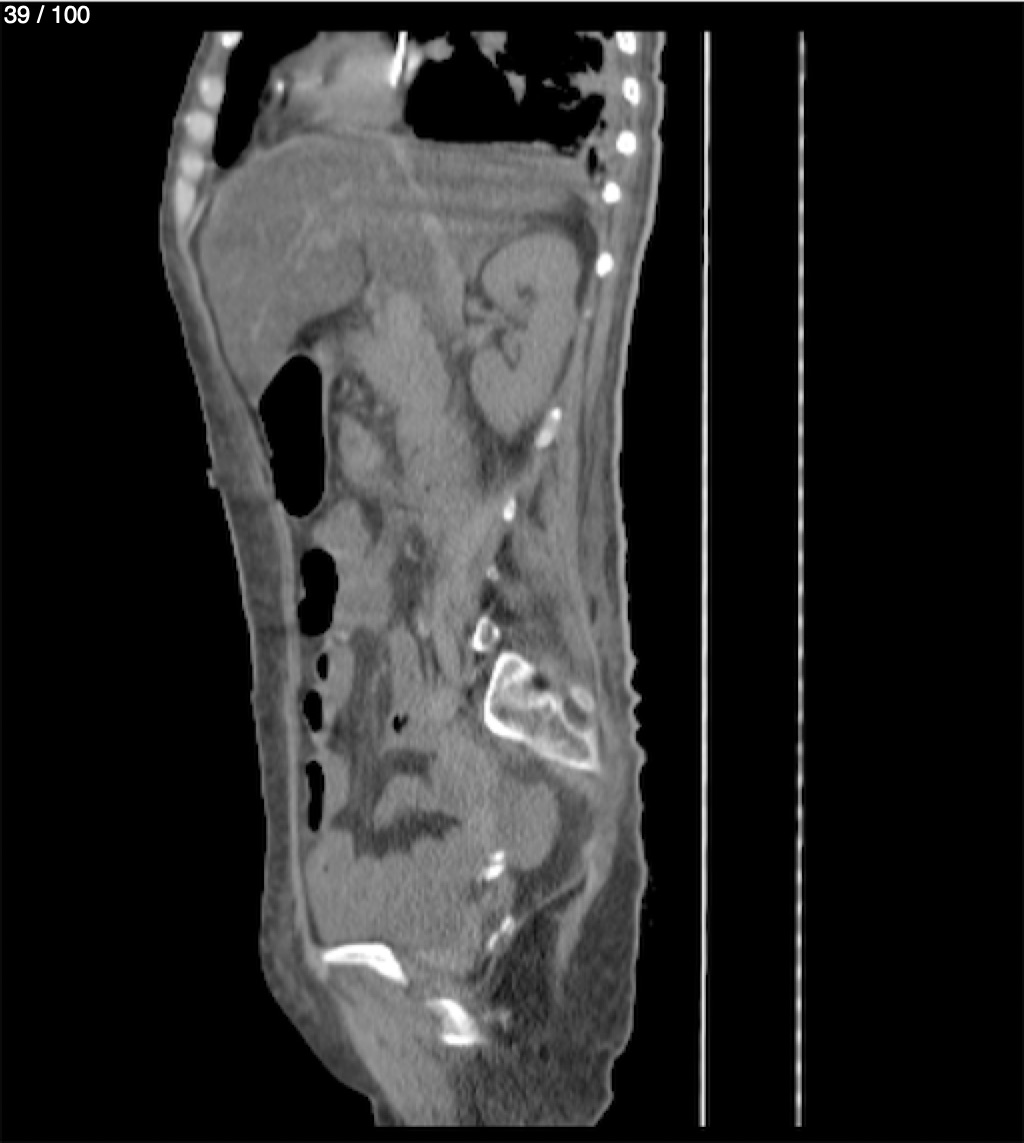

Hilda Geronimo Mendez 60A - T.C Abdomen Simple